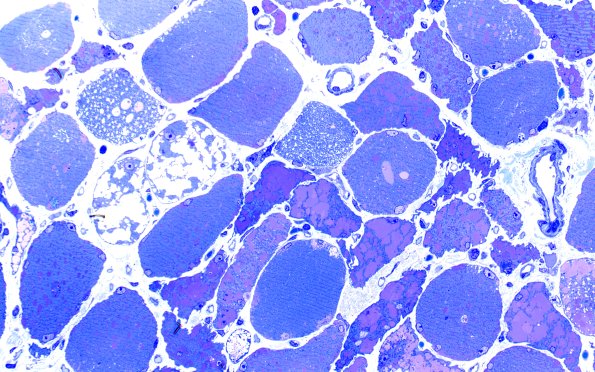

5C6 Muscle (Case 5) Plastic 40X 1

5C6-8 Several fibers are particularly vacuolated with variable content. (Plastic sections)